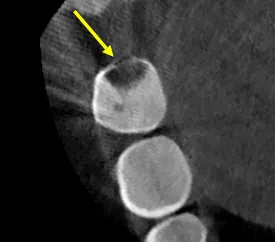

C-shaped canals occur in approximately 30-45% of mandibular second molars in certain populations, but they're rarely encountered by general dentists because the anatomical variation isn't visible on standard radiographs. This patient's CBCT revealed a Type I C-configuration—a continuous ribbon of pulp tissue connecting what would normally be separate mesial and distal canals.

• Radiographs that show "merging" canals in mandibular molars suggest C-shaped anatomy

When these signs appear, CBCT imaging should be obtained before proceeding. Attempting to treat C-shaped canals without understanding the anatomy leads to incomplete cleaning and treatment failure.

• CBCT: Essential for visualizing the three-dimensional C-configuration